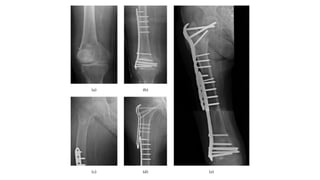

This document discusses femoral fractures, categorized by their location and severity, with classifications such as Garden classification. It outlines the types of fractures, including valgus impacted, non-displaced, partially displaced, and fully displaced, along with their surgical treatment options. Additionally, it briefly describes distal femur fractures, which occur just above the knee joint.